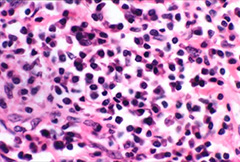

C-reactive protein (CRP) is an annular (ring-shaped), pentameric protein found in blood plasma, whose levels rise in response to inflammation. It is an acute-phase protein of hepatic origin that increases following interleukin-6 secretion by macrophages and T cells. ... Read Article

Complete Blood Count - Sinoe Medical Association

Monocytes: The normal monocyte count is 100 to 700 cells/ L of blood. Monocytosis, an elevated monocyte count, is indicative of chronic inflammation, ... Retrieve Document